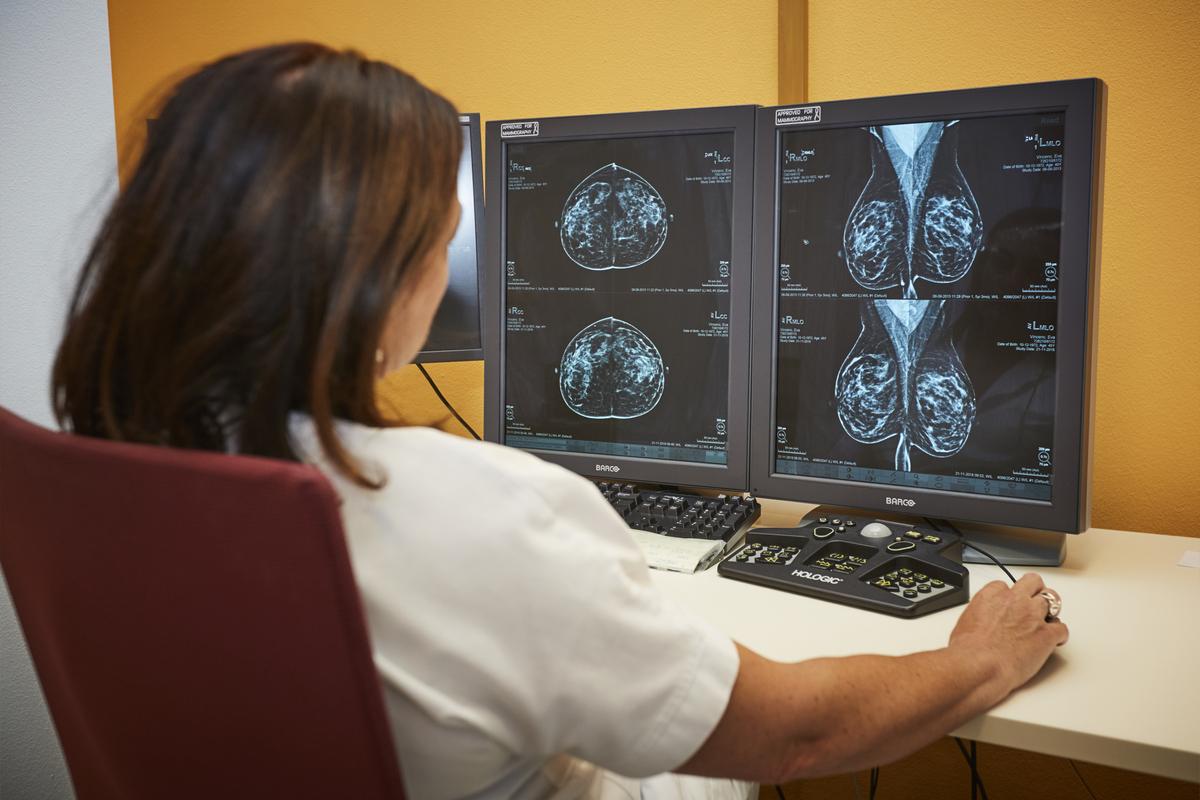

Významným krokom v skvalitnení diagnostiky bola výmena špeciálneho stereotaktického bioptického stola v roku 2024. Nemocnica tak po 15 rokoch investovala viac ako 230 000 eur do nového zariadenia, ktoré prináša výrazne vyššiu kvalitu zobrazenia a efektívnejší priebeh vyšetrenia.

Nový bioptický stôl má výrazne väčšie zorné pole, čo umožňuje presnejšie zameranie aj drobných lézií. Automatizované funkcie zároveň zjednodušujú pracovné postupy zdravotníckeho personálu a znižujú riziko manuálnych chýb. Technológia poskytuje lekárom 360-stupňový prístup k prsníku, čo je výhodné najmä pri ťažšie dostupných nálezoch, a zároveň zvyšuje komfort pacientiek počas samotného zákroku.